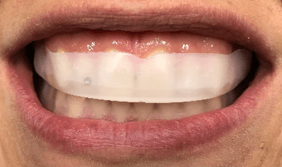

Unaprijed napunjene, konfekcijske Opalescence Go udlage nose se 60–90 minuta dnevno, tijekom 7-10 dana, što ih čini fleksibilnim za upotrebu – čak i spontano ili ‘usput’. Nakon čišćenja zuba uređajem za mikro-pjeskarenje, postavili smo prvu Opalescence Go udlagu (gornji i donji luk) u ordinaciji.

Slika 2: Opalescence Go gornja udlaga